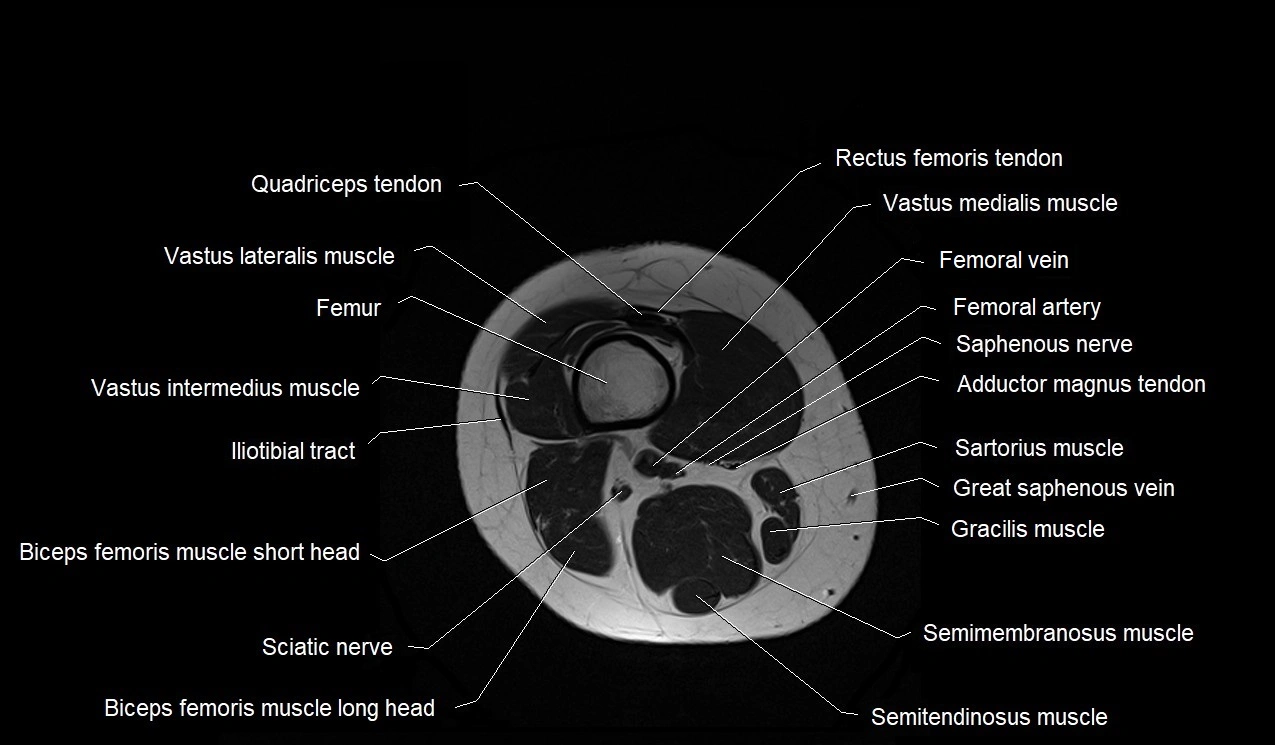

- Biceps femoris muscle (Long head)

- Biceps femoris muscle (Short head)

- Femoral artery

- Femoral nerve

- Femoral vein

- Femur

- Gracilis muscle

- Iliotibial tract

- Rectus femoris muscle

- Sartorius muscle

- Semimembranosus muscle

- Semitendinosus muscle

- Vastus intermedius muscle

- Vastus lateralis muscle

- Vastus medialis muscle